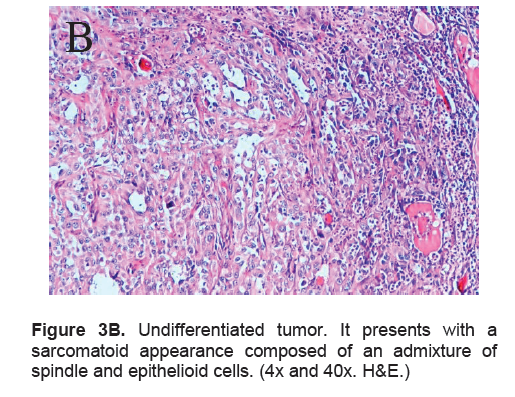

The right lobe measured 8.3 x 6.0 x 4.3 cm, and weighed 119.5 grams with a tan brown surface covered with fibrous tags (Figure 3A). Cut sections showed an ovoid mass, 6.7 x 5.2 cm in greatest dimensions, with a thin capsule and yellow-tan, gritty to mucoid cut surface with areas of hemorrhage and necrosis. The tumor infiltrated and replaced normal thyroid parenchyma and was surrounded by a thin capsular rim. Tissue sections of the right lobe revealed an infiltrative tumor composed of an admixture of pleomorphic cells, spindle cells and occasional tumor giant cells (Figure 3B). There were small areas showing reminiscent papillary or microfollicle pattern, while some areas showed large epithelioid or multinucleated tumor cells with bizarre nuclei (Figure 3C). Capsular (Figure 3D) and vascular (Figure 3F) invasion were present with extensive tumor necrosis. The uninvolved right and left lobes showed multinodular colloid goiter with lymphocytic thyroiditis. It was signed out as an Anaplastic (undifferentiated) thyroid carcinoma of the right lobe.

Click here to download Figure 3B

Figure 3B. Undifferentiated tumor. It presents with a sarcomatoid appearance composed of an admixture of spindle and epithelioid cells. (4x and 40x. H&E.)